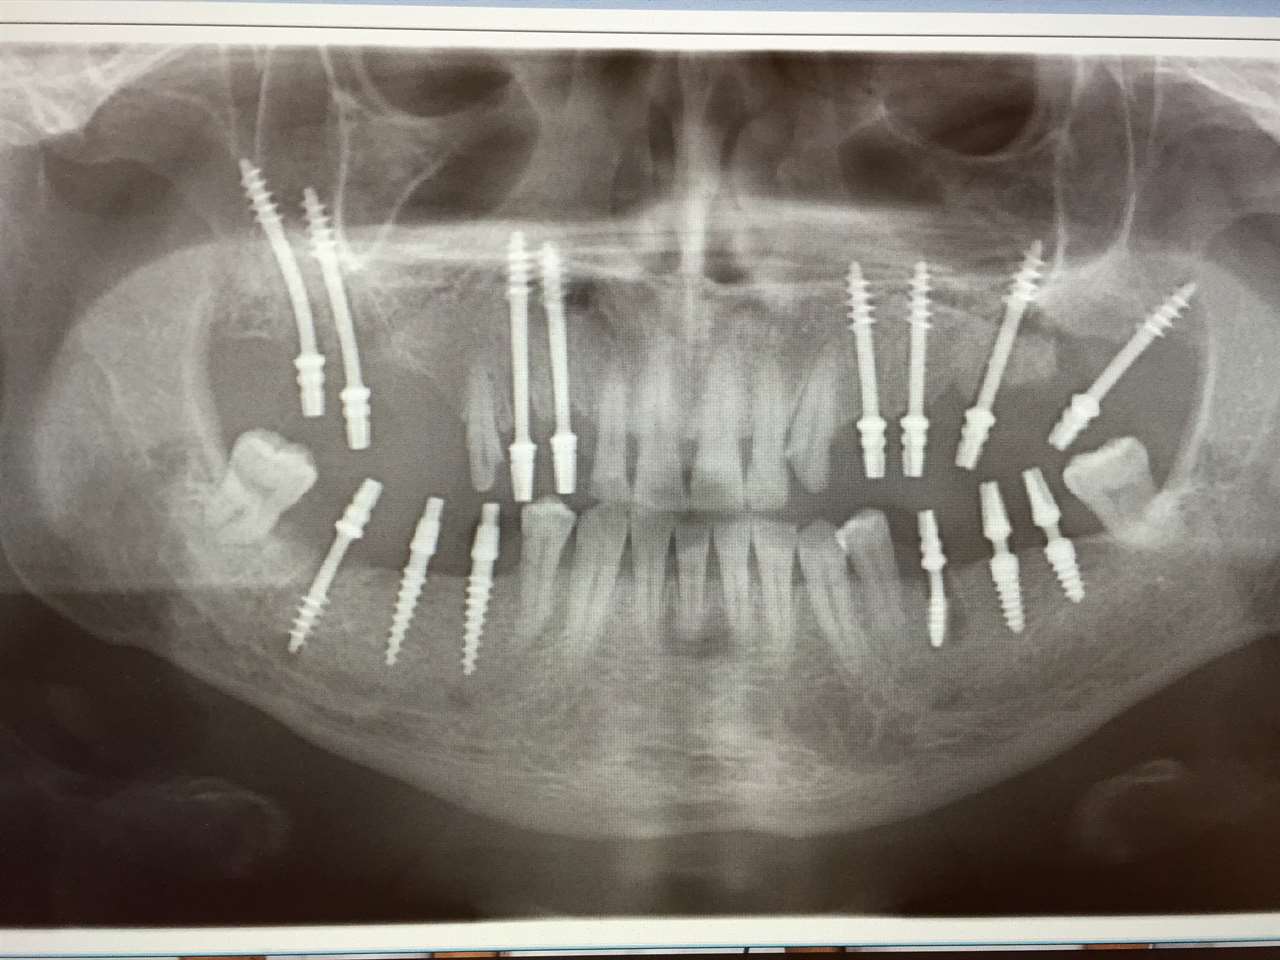

Teljes fogatlanság helyreállítása 2 nap alatt

Teljes fogatlanság helyreállítása 2 nap alatt azonnal terhelhető svájci IHDE implantátumokkal és PMMA műanyag hidakkal. Intraorális szkennerrel vettünk lenyomatot az implantáció után, és erre a digitális mintára készítette el a fogtechnika a hidak digitális tervezését, majd faragta ki műanyagból. Ezt a gyors munkát az azonnal terhelhető implantátumok és a digitális lenyomat, tervezés segítségével tudtuk megcsinálni mindössze 2 nap alatt. Dr. Kelemen Péter és a Symbion Fogtechnika munkája.